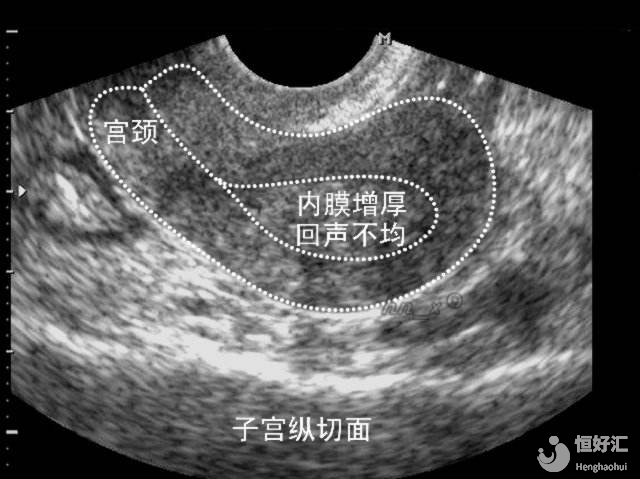

我們首先要了解一點(diǎn),子宮內(nèi)膜的厚度并未一成不變的,它會(huì)隨著月經(jīng)周期的變化而變化。在月經(jīng)期、增生期和分泌期這三個(gè)階段,都會(huì)出現(xiàn)不同的厚度變化。

月經(jīng)退潮后,卵泡便開始生長(zhǎng),子宮內(nèi)膜在雌激素的作用下開始變厚,一直到月經(jīng)終止前,子宮內(nèi)膜才算完成“修復(fù)”,然后再到增生晚期。

這時(shí)子宮內(nèi)膜厚度一般會(huì)加厚到9mm-10mm左右。

這一階段的卵巢已經(jīng)排過卵了,在孕激素的作用下,子宮內(nèi)膜會(huì)持續(xù)增厚,并且會(huì)變得越來越柔軟。

分泌期晚期的子宮內(nèi)膜會(huì)呈現(xiàn)海綿狀,子宮內(nèi)膜厚度則會(huì)增厚到10mm-12mm左右。

子宮內(nèi)膜并不是越厚越好

子宮內(nèi)膜對(duì)試管嬰兒的妊娠成功率確實(shí)是關(guān)鍵,但并不是越厚就越好的,這個(gè)問題本身并不是絕對(duì)的。

部分研究認(rèn)為,子宮內(nèi)膜厚度越厚,那胚胎移植率就會(huì)越高;但同時(shí)也有一些研究數(shù)據(jù)表示,當(dāng)子宮內(nèi)膜厚度一旦高于14mm時(shí),胚胎移植成功率是不可觀的。

通常來說,子宮內(nèi)膜厚度能達(dá)到8mm-13mm左右,那么這時(shí)就可以去進(jìn)行試管嬰兒胚胎移植了。

所以,大家在進(jìn)行胚胎移植時(shí),子宮內(nèi)膜厚度能夠達(dá)到7mm以上,在8mm-13mm之間,那么就可以開始準(zhǔn)備去移植了。